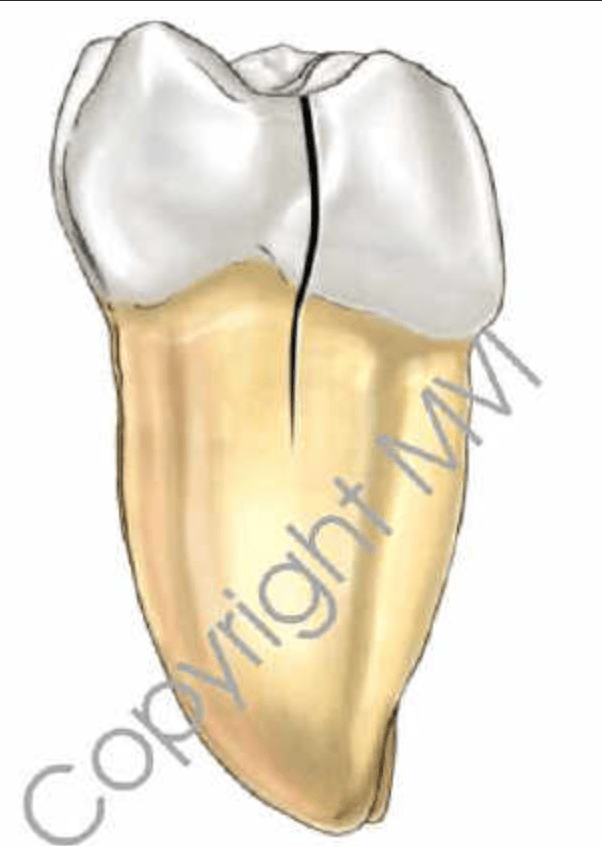

Diente fisurado, no tratable

Diente fisurado tratable

Vertical root fracture